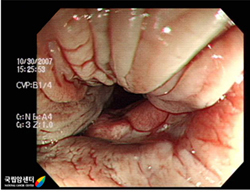

항문암 외에 대장에 다른 병변이 있는지 확인하기 위해 시행합니다. 대장내시경검사란 내시경으로 대장을 직접 보는 검사 방법으로 대장질환 검사에서 가장 정확한 진단방법입니다. 그 이유는 의사가 직접 병변의 표면을 관찰하거나 조직 상태를 파악할 수 있기 때문입니다.

내시경검사와 동시에 조직검사도 가능합니다. 짧은 시간 동안만 작용하는 진정제(수면제)를 정맥 주사하여 수면 상태와 비슷한 상태에서 큰 불편감 없이 내시경 검사를 시행받을 수 있는 진정하 대장내시경(수면 대장내시경)검사도 있습니다. 정확한 검사를 위해 환자는 전날 저녁식사는 등으로 가볍게 하고 하제를 복용하여 대장 내에 남아있는 분변을 제거해야 합니다.

[ 항문암의 대장내시경 소견 ]